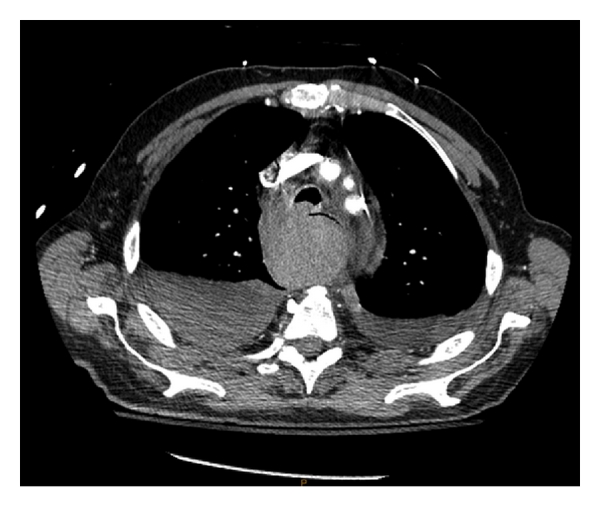

Repeat CT scan at MGH confirmed the presence of a posterior mediastinal hematoma with bilateral hemopneumothorax, in addition to a fracture of the inferior right facet joint of the C7 vertebrae (not shown) (Figures 1 and 2). The patient was intubated in the ER due to concern regarding the possibility airway compromise, secondary to an expanding hematoma. The patient was then transferred to the ICU where initial management included a complete blood count (continued in series), c-spine immobilization with a rigid cervical collar and cessation of all anticoagulation medication, with concurrent rate control for the patient’s preexisting atrial fibrillation.

On day one of admission, the patient’s vital signs and hemoglobin levels remained stable. The patient was extubated without difficulty. Repeat CT scans of the chest indicated no enlargement of the hematoma or structural abnormalities of the Thoracic aorta (i.e., dissection, aneurysm). Consults to orthopedic surgery and cardiothoracic surgery were placed to assess the patient’s cervical fracture and hematoma. It was determined that since both injuries were stable, conservative management would be maintained. Daily chest X-rays were ordered to assess the resolution of the patient’s hemothoraces. Evacuation of the hemothoraces via chest tube drainage was considered but deferred, as follow-up CT scans on Hospital days (HDs) two and four demonstrated a decrease in the size of both the hematoma and hemothoraces (Figure 3). The patient was transferred from the ICU to a surgical floor on HD two. Physical examination of the patient on HD four demonstrated stable vital signs, resolution of chest pain, and no reports of dysphagia, dyspnea, or dysphonia.